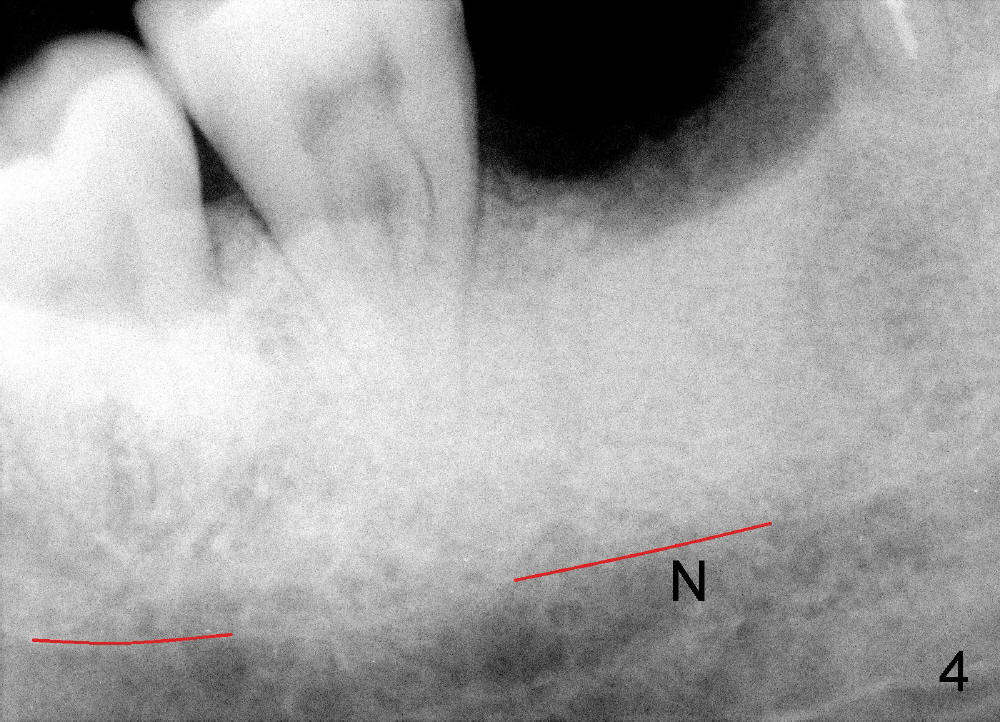

A 46-year-old man has severe periodontitis. The tooth #30 is complicated by incomplete root canal therapy (Fig.1,2). Three months after extraction (Fig.3-5: N: inferior alveolar canal), a 5x14 Tatum tapered implant is placed (Fig.6,7). The problem is that an implant driver is fractured (D in Fig.7), while the implant is being torqued. It takes time and effort to remove the fractured driver, but the implant is solid. The healing screw is placed without difficulty (Fig.8). Since the implant is placed lower than the lingual gingiva (L in Fig.9), a healing cuff is placed 1.5 months after implant placement (Fig. 10 and 11: C) to push the lingual gingiva down. The X-ray appears to show lower bone density around the implant (bone necrosis?), although the implant has no mobility at all. Since the implant is so solid, can we load it, two months after surgery? The lingual gingiva is now lower than the healing cuff (not shown). CT is scheduled to be taken tomorrow. Thanks.